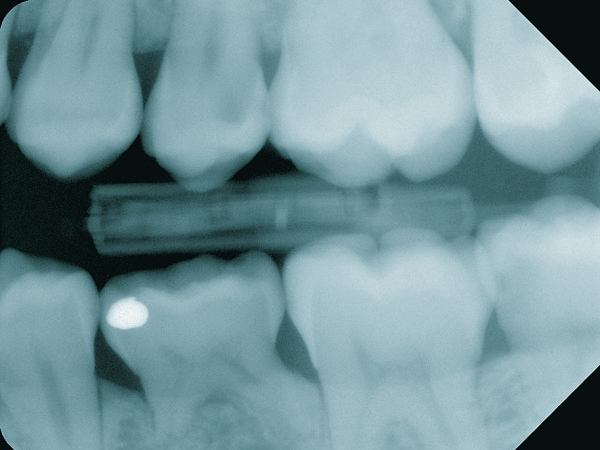

Insgesamt lagen in der Untersuchung 73 Prozent der mittels Röntgen entdeckten Schmelzläsionen und solche mit noch nicht eingebrochener Oberfläche im Approximalraum, nur 0,7 Prozent okklusal. (Das Foto zeigt einen Karies- Zufallsbefund an Zahn 25 bei einer 24-jährigen Patientin.)

Bei der klinischen Kariesdiagnostik im Approximalraum lag die Fehlerquote der Behandler bei zehn Prozent. So hoch war der Anteil an für gesund gehaltenen Approximalflächen, die radiologisch eine Kariesläsion im Schmelz-/Dentinbereich aufwies. Insgesamt lagen 73 Prozent der mittels Röntgen entdeckten Schmelzläsionen und solche mit noch nicht eingebrochener Oberfläche im Approximalraum, nur 0,7 Prozent okklusal. Mehr als die Hälfte der approximalen Dentinläsionen (61 Prozent) entdeckten die Forscher nur über ein Röntgenbild. Mehr als die Hälfte der okklusalen Dentinläsionen (57 Prozent) detektierten sie dagegen ausschließlich klinisch.